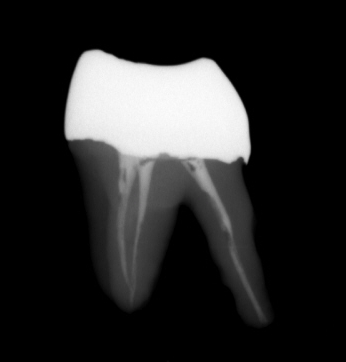

レントゲン左下に横向いている歯が親知らずです。